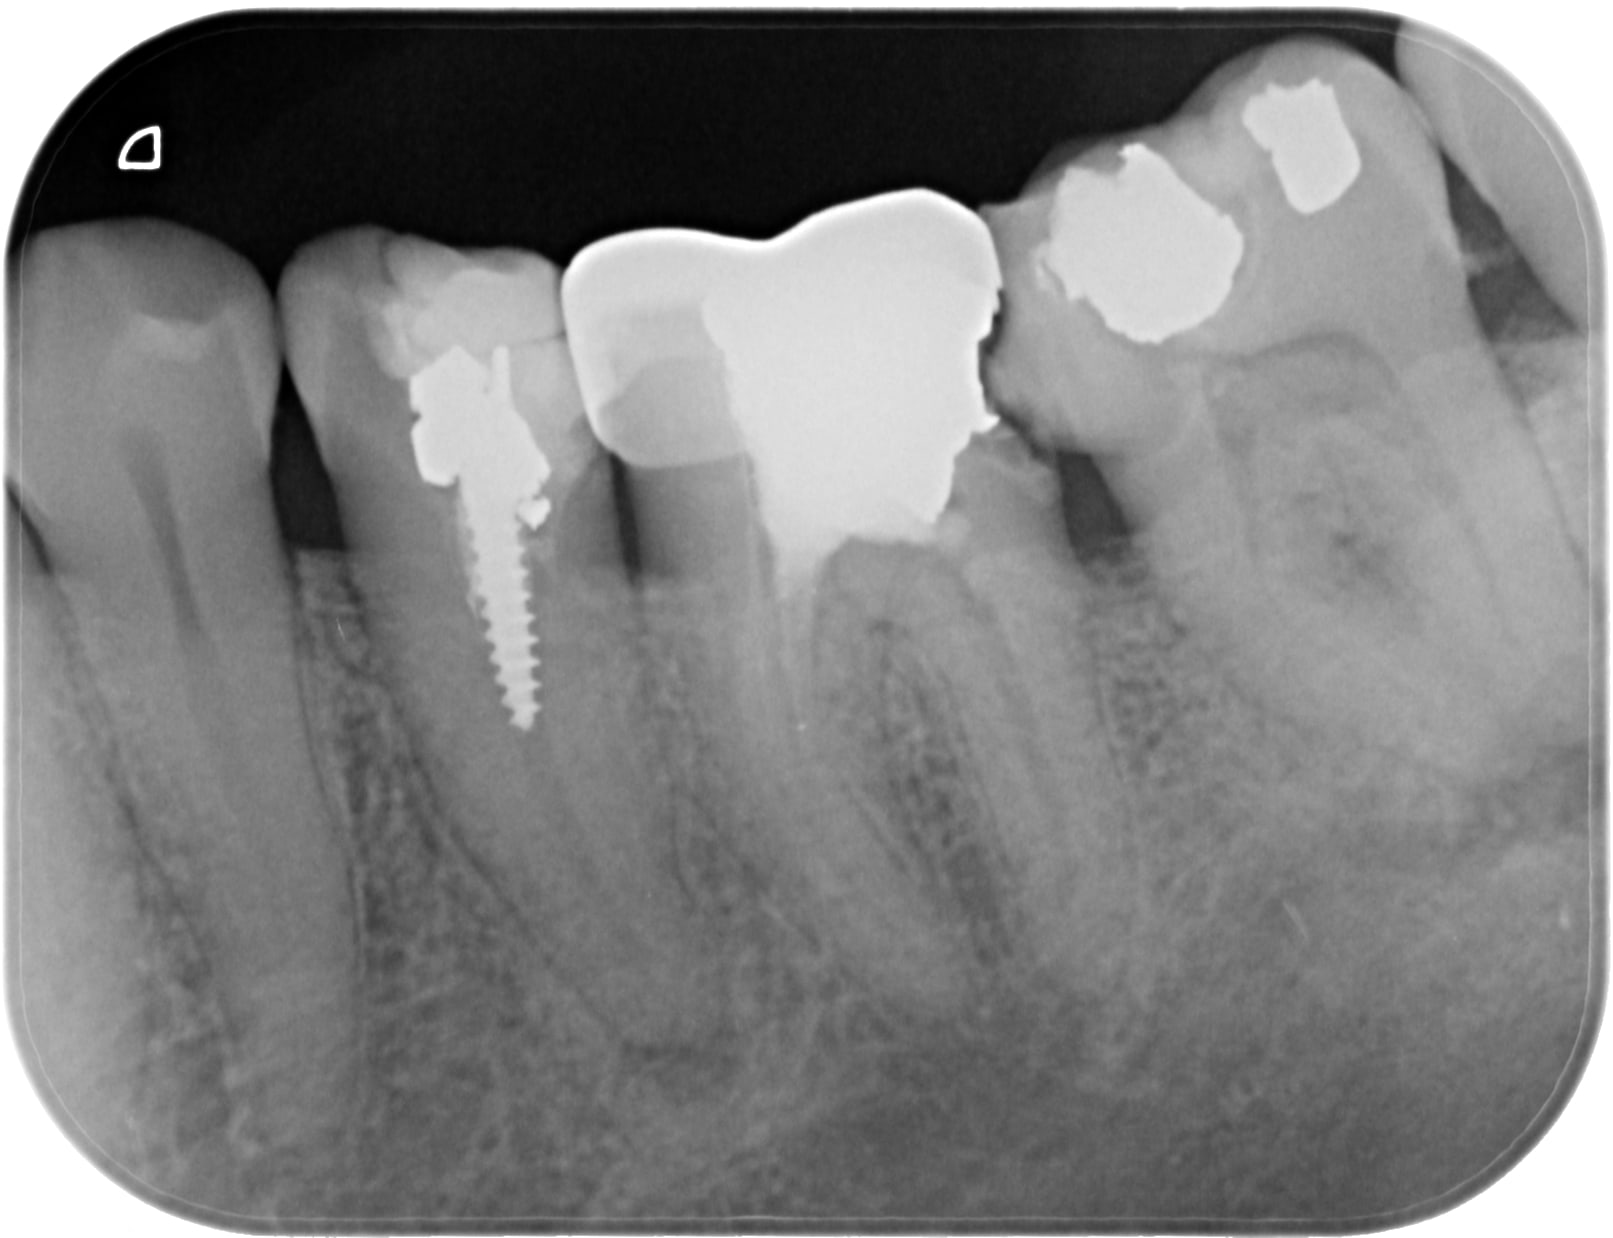

Une patiente se plaint en fin de rendez vous ... du temps passé à faire son tt endo, du fait que je lui ai posé la digue ... et que "elle n'a jamais connu ça de sa vie et pourtant des traitements de racine elle en a dejà eu un paquet " ... Pas de doute en voyant la radio pré op

B1 axheps - Eugenol